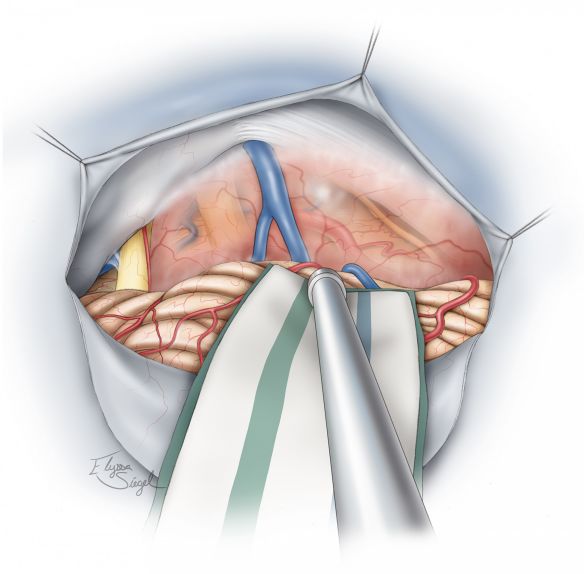

图11. 在肿瘤壁外分离完肿瘤后,切除肿瘤的幕下部分。

图12. 切除肿瘤后可见后颅窝的解剖,如图显示了乙状窦后和小脑上入路的手术通道。

图13. 电凝小脑幕的下表面然后切开一个宽大的硬脑膜窗暴露幕上的肿瘤部分。用Karlin刀片平行于横窦切开小脑幕,外侧沿着岩骨嵴,内侧沿着直窦边缘切开小脑幕,小脑幕游离缘的出血可通过明胶海绵压迫止血。

图14. 幕上部分的肿瘤切除后可以看见最终的瘤腔解剖。如有必要,翻开岩骨嵴上的硬脑膜,切除第V颅神经上方向岩尖方向的骨质,可以将手术通道扩大越过岩骨嵴从而达到中颅窝的外侧部分。